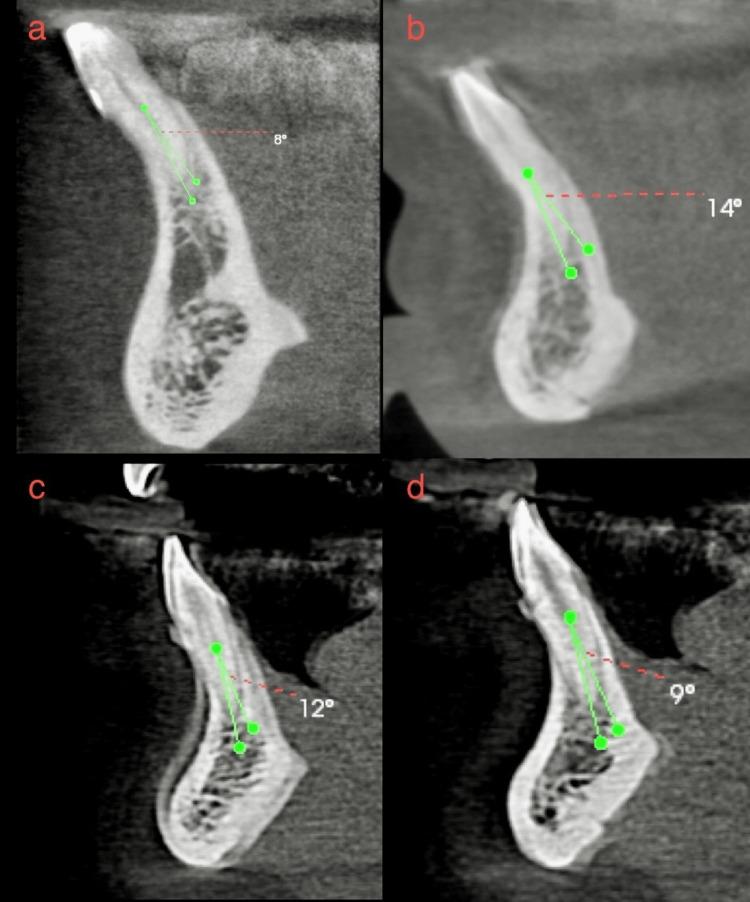

Aim Using two classifications, this study assessed root morphology and canal configuration and measured the Dentin thickness (DT) and canal shapes. Methods Cone beam computed tomography (CBCT) with 400 Mandibular Incisors was collected and assessed for the number, length, curvature of roots, number of canals, bifurcation level, configurations based on Vertucci's and Ahmed's classification, DT and canal shape at 3, 6, 9 mm from the apex. The collected data was subjected to statistical analysis with a level of significance at p<0.05. Results All samples had one root, averaging 12.769 ± 1.128 mm in central incisor (CI) and 13.044 ± 1.235 mm in lateral incisor (LI), with most roots being straight. Most samples had one canal in both teeth, with bifurcations most frequent in the middle third. The most frequent configuration was type 1 Vertucci or CI/LI by Ahmed, followed by type 3 or CI/LI. One sample, not classifiable under Vertucci, was classified as CI by Ahmed. The mean DT for CI was 3.18 ± 0.639 mm, 3.72 ± 0.671 mm and 4.43 ± 0.754 mm labiolingually and 1.578 ± 0.342 mm, 1.881 ± 0.374 mm, 2.283 ± 0.465 mm mesioditally at 3, 6, 9 mm from the apex, respectively. For LI, mean DT was 3.41 ± 0.916 mm, 3.90 ± 0.702 mm and 4.55 ± 0.746 mm labiolingually and 1.63 ± 0.322 mm, 1.981 ± 0.485 mm, 2.55 ± 0.470 mm mesioditally at 3, 6, 9 mm from the apex respectively, canal shape changed from oval to round, from apical to coronal. Conclusion Single canals were the most common, followed by two canals. The middle third of the canal had the most bifurcations. Vertucci type 1 or Ahmed's CI/LI  was the most commonly reported canal configuration, with one sample that could not be classified under Vertucci but could be classified using Ahmed classification. DT increased apical to coronal. The canal shape changed from oval to rounded, from apical to coronal.

目的 本研究使用两种分类方法评估牙根形态和根管形态,并测量牙本质厚度(DT)和根管形状。方法 收集400颗下颌切牙的锥形束计算机断层扫描(CBCT)图像,评估牙根的数量、长度、弯曲度、根管数量、分叉水平,根据Vertucci分类法和Ahmed分类法评估根管形态,测量根尖3、6、9 mm处的DT和根管形状。对收集的数据进行统计学分析,显著性水平为p<0.05。结果 所有样本均有一个牙根,中切牙(CI)平均长度为12.769±1.128 mm,侧切牙(LI)平均长度为13.044±1.235 mm,大多数牙根为直根。大多数样本的两颗牙均有一个根管,分叉最常见于中1/3处。最常见的形态为Vertucci分类法中的1型或Ahmed分类法中的CI/LI,其次是3型或CI/LI。有一个样本无法按照Vertucci分类法分类,但按照Ahmed分类法可归为CI。CI在根尖3、6、9 mm处的唇舌向平均DT分别为3.18±0.639 mm、3.72±0.671 mm和4.43±0.754 mm,近远中向平均DT分别为1.578±0.342 mm、1.881±0.374 mm和2.283±0.465 mm。LI在根尖3、6、9 mm处的唇舌向平均DT分别为3.41±0.916 mm、3.90±0.702 mm和4.55±0.746 mm,近远中向平均DT分别为1.63±0.322 mm、1.981±0.485 mm和2.55±0.470 mm,根管形状从根尖向冠方由椭圆形变为圆形。结论 单根管最为常见,其次是双根管。根管的中1/3处分叉最多。Vertucci 1型或Ahmed的CI/LI是最常报道的根管形态,有一个样本无法按照Vertucci分类法分类,但可按照Ahmed分类法分类。DT从根尖向冠方增加。根管形状从根尖向冠方由椭圆形变为圆形。